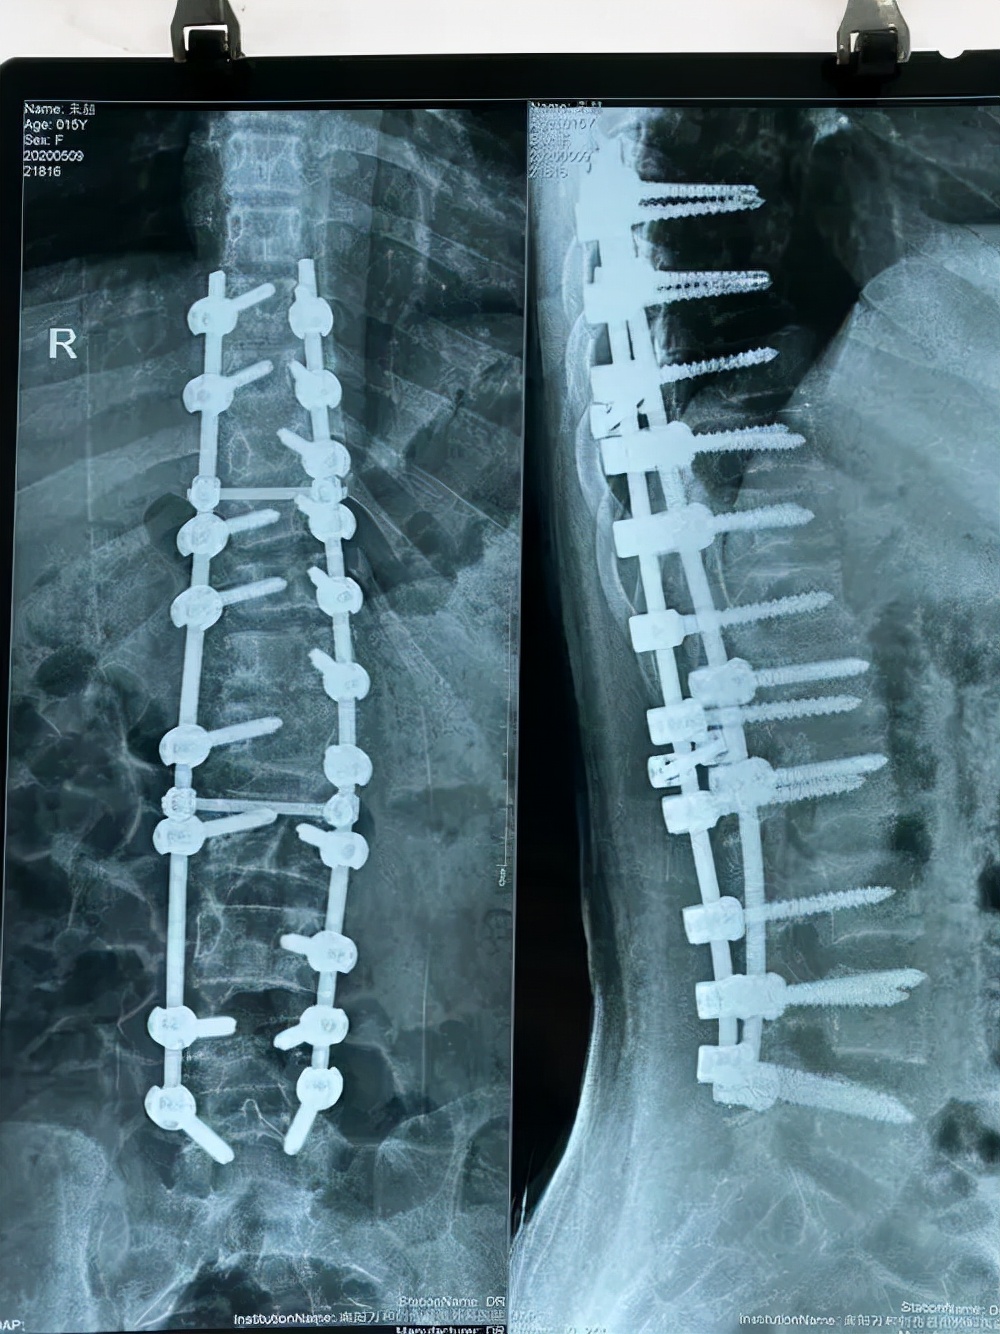

治疗脊柱侧弯主要围绕这四个方面:减缓脊柱侧弯的发展、减轻脊柱侧弯的症状、恢复脊柱的平衡、矫正畸形。在进行手术之前,医生会评估患者的情况,确定手术的风险,若是矫正畸形后的后果患者无法承受,或者风险太高,医生会选择相对稳妥的方案进行手术。

除患者身体导致的手术风险外,主刀医生的技术和手术设备也会影响手术安全。脊柱侧弯的手术涉及到脊髓、脊柱、神经等重要的组织,风险远超普通的外科手术。所以,是否由一位手法熟练的医生主刀是手术是否安全至关重要的因素。

第二点就是手术设备的问题。脊柱侧弯的修复很大程度上依赖于医生的熟练程度,也需要手术设备的支持。先进的导航设备可以帮助医生寻找合适的固定位置;神经监护设备能时刻注意神经是否有损伤,防止意外的发生。

所以说,脊柱侧弯手术确实有风险,但先进科学的手术设备、技术成熟可靠的医生、详细的手术方案,这三者相辅相成,已经大幅度地降低了手术过程中的风险。因此,不必过于担心手术的风险,相信医生,做出正确的决定即可。

每个省、市的治疗花费不同,且病情严重程度不同,手术的费用也不相同。这是去年十月的一场手术,总花费12.8万报销7.5万左右,报销比例58%左右。从这则手术来看,脊柱侧弯手术费用并不是很高,且还能享受高额的报销,并不是很多患者说的治疗一次就会倾家荡产。